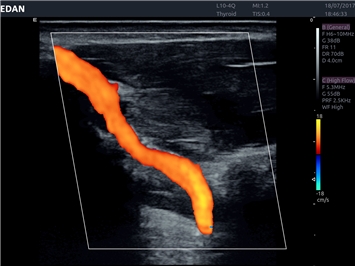

• Сосудистой диагностики

Цветовой допплер:

Да

Импульсно-волновой допплер:

Дуплексное сканирование: